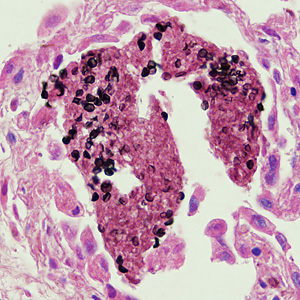

27yo man w/hiv; 10-day hx of fever, chills, malaise, yellow sputum. CD4 = 24, high viral load.

broad-based budding, similar size as RBC

blastomyces dermatitidis

endemic to missi/ohio river valleys.

tx with amphotericin b or azoles

from lung, hiv+

pneumocystis cyst